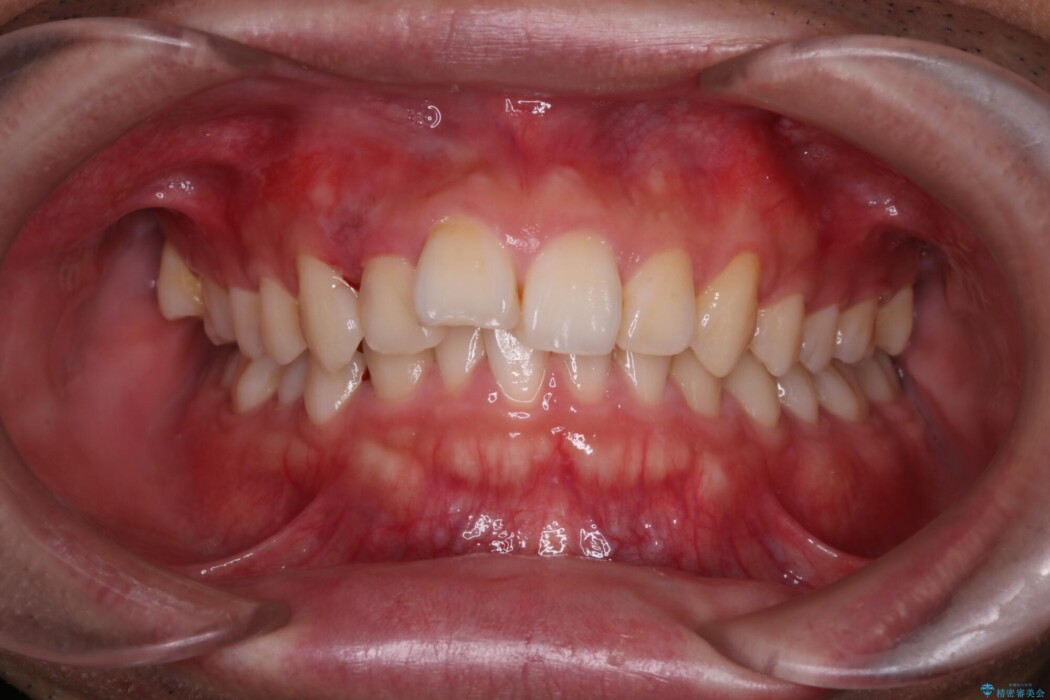

前歯のガタつきを改善したいとのことで他院にて相談をしたところ抜歯矯正を提案され、患者様としては非抜歯での治療をご希望とのことで来院されました。

検査したところ叢生量などを考慮し当院の判断として非抜歯での治療が可能と判断しました。

特に下顎前歯の叢生(がたつき)につきましては、きれいに配列させるだけのスペースが現状なかったため、遠心移動とIPR(歯と歯の間を少し削る)を行うことで確保しました。